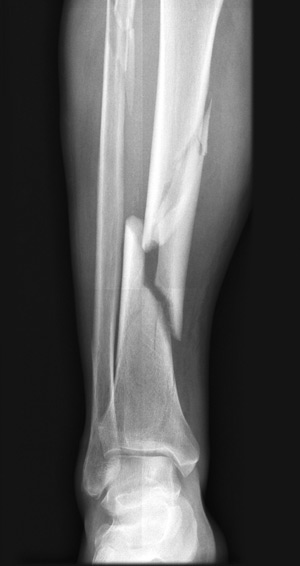

Comminuted tibial fractures